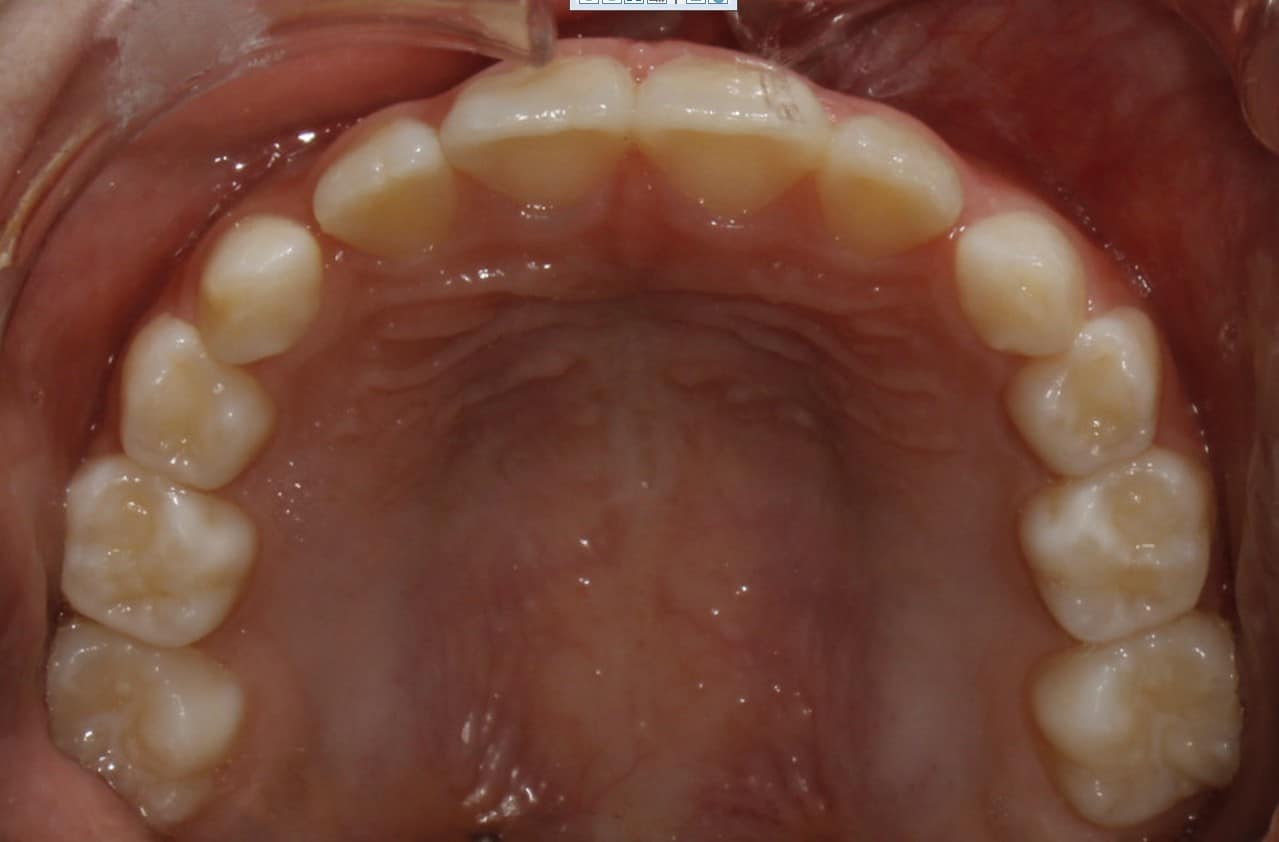

Phase I treatment with an Expander and Invisalign aligners

Phase I treatment with an Expander and Invisalign aligners to create space for permanent teethÂ